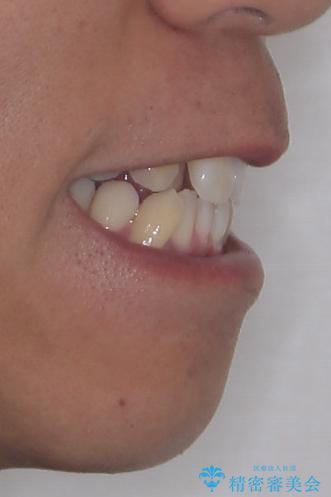

八重歯はきれいに整い、前歯もバランスよく収まり、横顔のラインも自然に改善されました。

治療後、患者様は「思い切り笑えるようになった」と大変喜んでくださいました。

治療前

• 八重歯と前歯のガタガタを抜歯矯正で治療|クリアブラケット使用例 治療前画像